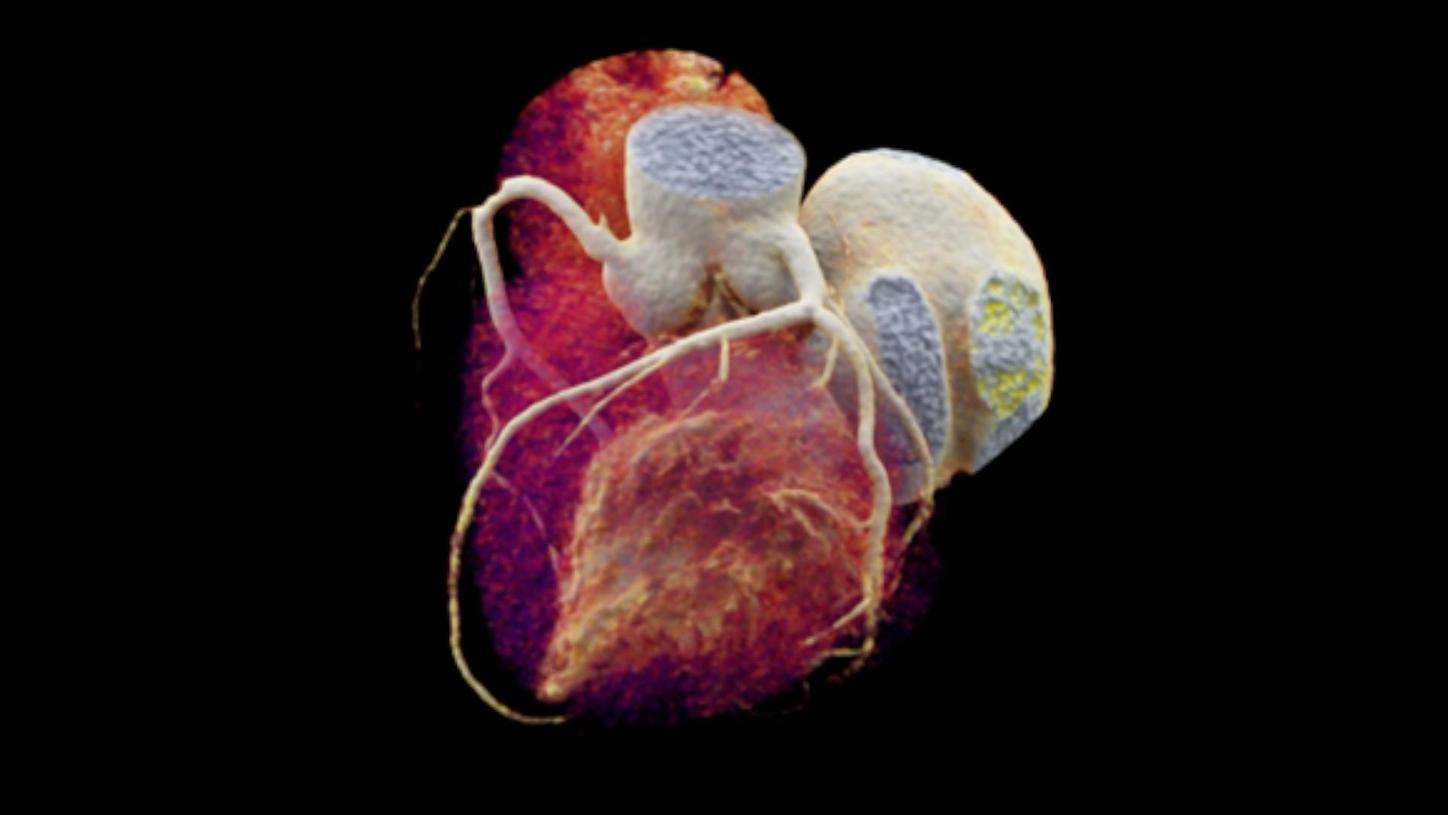

Coronary artery disease:  Imaging of the heart used for coronary artery diagnosis

Coronary artery disease

Coronary artery disease (CAD) is the number one cause of death globally, with numbers rising every year. To help medical practitioners increase the life expectancy of their patients, Siemens Healthineers offers a wide portfolio of imaging solutions supporting minimally invasive therapies including the treatment of CAD.